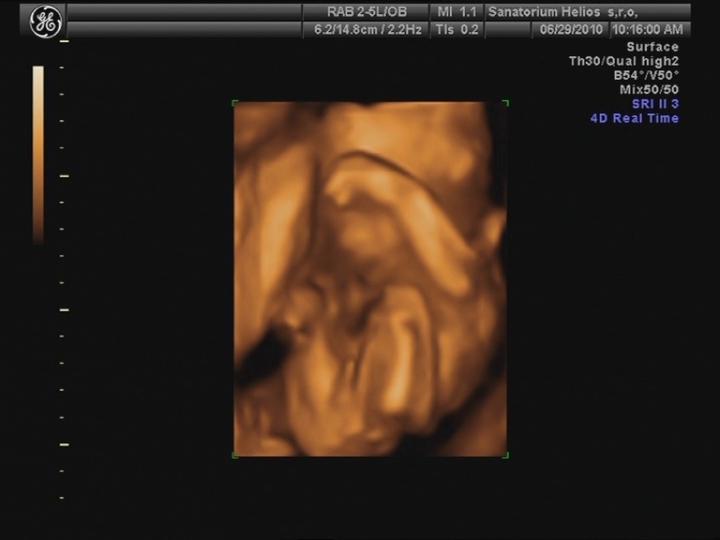

25.5. jsme vstoupili do 5. měsíce .... nečekaně se to pohlo 🙂